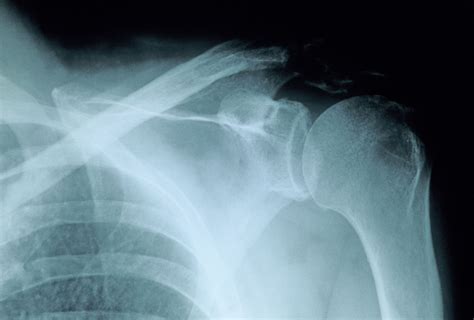

• X-rays: Imaging tests such as X-rays are used to visualize the bone and determine the type and severity of the fracture.

Proximal Humerus Fracture Occurs near the shoulder joint, often involving the head or neck of the humerus.